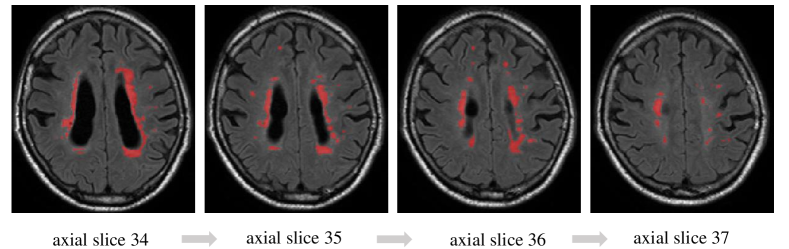

Different from brain tumor segmentation [5] in MR images where most of the abnormal regions are large and with spatial continuity, in the task of WMH segmentation, both large and small lesions with high discontinuity are commonly found as shown in Fig. 1. Generally, small abnormal region contains relatively less contextual information due to the poor spatial continuity. Furthermore, the feature representation of small lesions tend to be trivial when image features are extracted in a global manner. One solution to tackle this issue is to use an ensemble model or aggregation model [9] to learn different attributes i.e., multi-levels of feature representation from the training data.

Figure 1: From left to right: axial slices from 34 to 37 of one case from the MICCAI WMH Challenge public training set, showing the high discontinuity of white matter hyperintensities. The red pixels indicate the WMH annotated by a neuroradiologist.